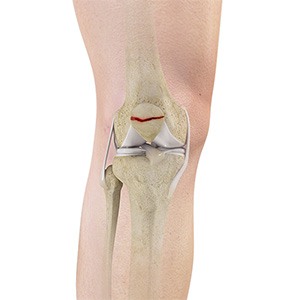

Picture of ACL Tears

ACL Tears

The anterior cruciate ligament (ACL) is one of the major ligaments of the knee. It is located in the middle of the knee and runs from the femur (thighbone) to the tibia (shinbone). The ACL prevents the tibia from sliding out in front of the femur. Together with the posterior cruciate ligament (PCL), it provides rotational stability to the knee.